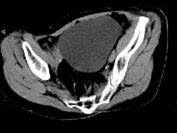

女, 62 岁, 左下腹持续性疼痛 3 天, 伴恶心、呕吐, 左侧附件区扪及一囊性包块, 活动, 表面光滑, 压痛明显,CT和MRI检查如图所示,下列说法...

问题 女, 62 岁, 左下腹持续性疼痛 3 天, 伴恶心、呕吐, 左侧附件区扪及一囊性包块, 活动, 表面光滑, 压痛明显,CT和MRI检查如图所示,下列说法错误的是 ( )

选项 A、结合临床症状,考虑为卵巢囊肿扭转 B、结合临床症状,考虑为卵巢囊腺瘤 C、该病灶包膜完整,边界清晰 D、膀胱向下压移位 E、左侧附件区一囊性占位性病变

答案 B